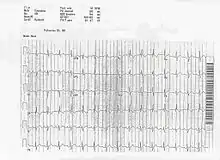

ECG of a patient with Ostium primum ASD

In the ECG above, you can see an example of the rSR' pattern in V1 with a R' greater than S with T wave inversion which is commonly seen in volume overload right ventricular hypertrophy.